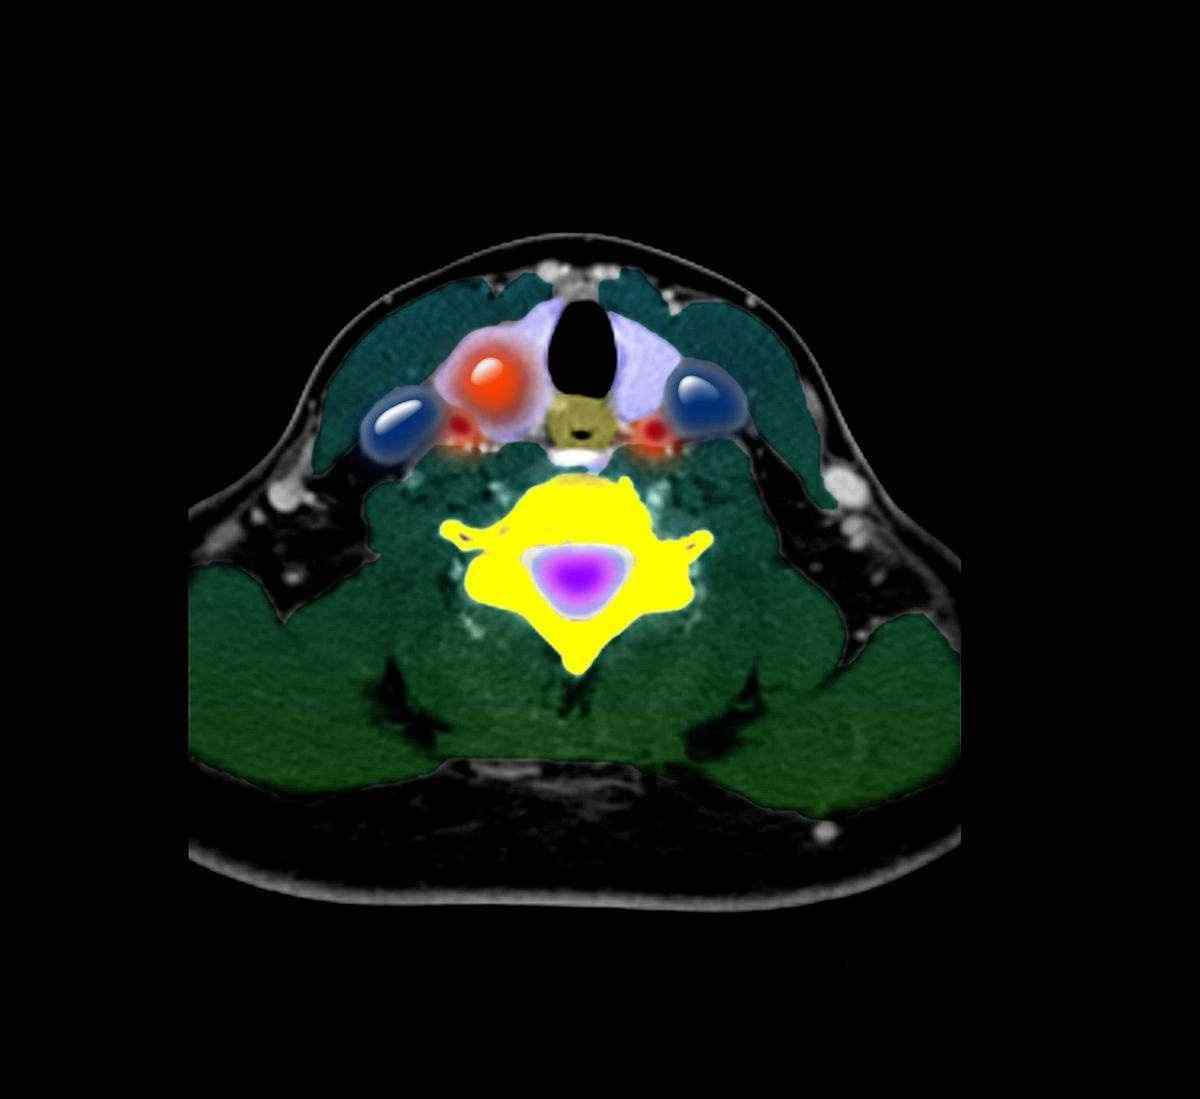

所以今天我们就普及一下甲状腺结节的相关信息。甲状腺是人体内的分泌腺之一,就像一只躺在人体气管前的小蝴蝶,其上的一种“小疙瘩”就是甲状腺结节。

甲状腺结节之所以听起来很危险,很陌生,是因为以前甲状腺结节的诊断都是靠手摸。现在在b超的“醒目”下,哪怕是最小的甲状腺结节也没有什么好隐瞒的。如果每个人都去医院做b超,身边一半的人都会有。